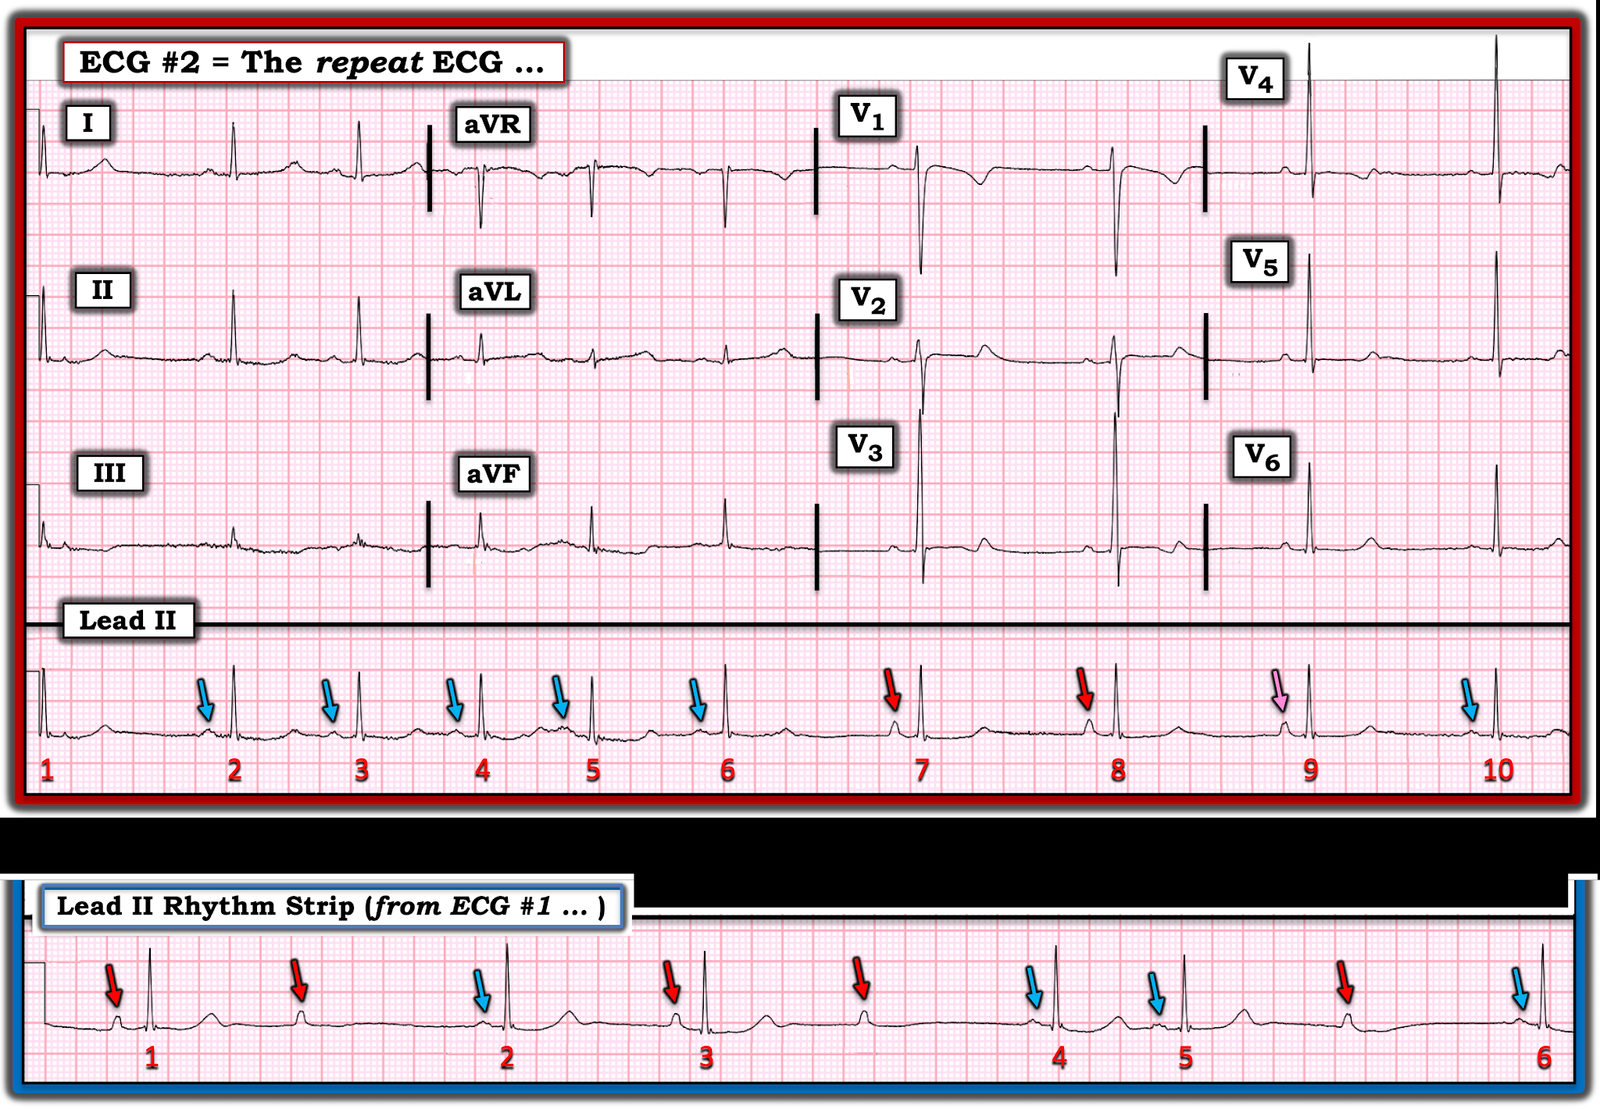

- Does this repeat ECG seen in Figure-3 provide some answers?

| Figure-3: The repeat ECG in today’s case. |

Our Thoughts After Seeing the ECG in Figure-3:

Immediately on seeing ECG #2 — Drs. Meyers, Smith and myself knew that my theory about artifact was not correct …

- Each QRS complex in the long lead II rhythm strip in Figure-3 is now clearly preceded by a conducting P wave.

For clarity in Figure-4 — I’ve labeled with colored arrows all P waves in the long lead II rhythm strips from the 2 ECGs done in today’s case.

- There are 2 atrial foci — which I represent with RED and BLUE arrows. I suspect that the deflections that I initially thought represented artifact (ie, the RED arrows) are sinus P waves — and that the BLUE arrows represent an atrial escape focus.

- Looking first at the long lead II rhythm strip in ECG #2 — the rhythm begins with 5 beats conducted by the escape focus (ie, beats #2-thru-6). The R-R interval from this escape focus begins to slow with beat #6 — after which the escape focus pauses …

- The sinus node “wakes up” with beat #7. Note that the PR interval preceding beats #7 and 8 is the same — proving these deflections are conducting.

- Beat #10 is once again conducted by the escape focus.

- The P wave preceding beat #9 is not quite as tall as the P waves preceding beats #7 and 8. I labeled this P wave with a PINK arrow in Figure-4 — as I believe it represents an atrial fusion beat that occurs during transition from sinus P waves to the escape atrial focus that takes over again with beat #10.